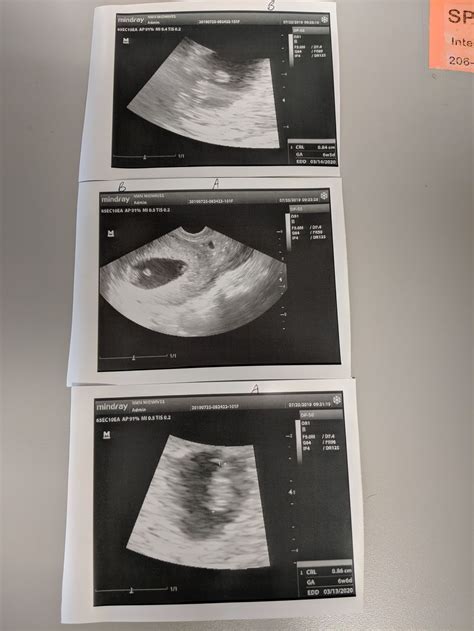

The Twins Week 7 Ultrasound is typically performed between 6 weeks and 8 weeks of pregnancy. At this stage, the embryos are still very small, but the ultrasound can detect important details about their development. The primary goal of this ultrasound is to confirm the presence of twins, determine the type of twins (identical or fraternal), and assess the overall health of the embryos.

• Confirmation of Twins: The ultrasound will confirm the presence of two gestational sacs, each containing an embryo.

• Heartbeat Detection: At this stage, the heartbeats of the embryos may be visible, although it is not always guaranteed. The heartbeat is a reassuring sign of development.

• Type of Twins: The ultrasound can sometimes determine whether the twins are identical or fraternal. Identical twins share a single placenta, while fraternal twins have separate placentas.

• Measurement of Embryos: The healthcare provider will measure the size of the embryos to ensure they are developing at the expected rate.

• Gestational Sacs: The presence of two gestational sacs confirms a twin pregnancy.

• Heartbeats: Detecting heartbeats in both embryos is a positive sign of development.

• Placenta and Amniotic Sacs: The ultrasound may show the number of placentas and amniotic sacs, which can indicate whether the twins are identical or fraternal.

• Measurements: The measurements of the embryos will be compared to standard growth charts to ensure they are developing normally.